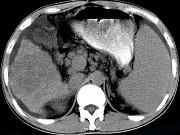

问题 男,35岁,有乙肝病史多年,AFP阳性,影像检查如图,最可能的诊断是()

选项 A.肝硬化腹水 B.肝血管 C.肝脓肿 D.肝癌、硬化腹水 E.肝硬化,结节性增生

答案 D